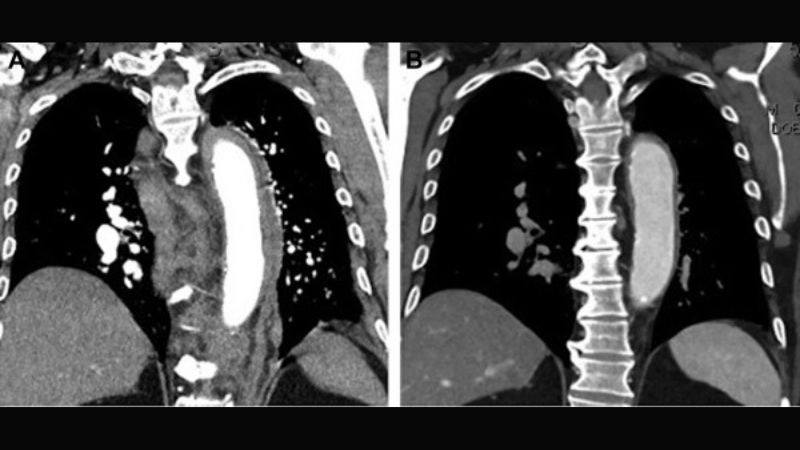

Takayasu arteritis as a rare vascular disorder